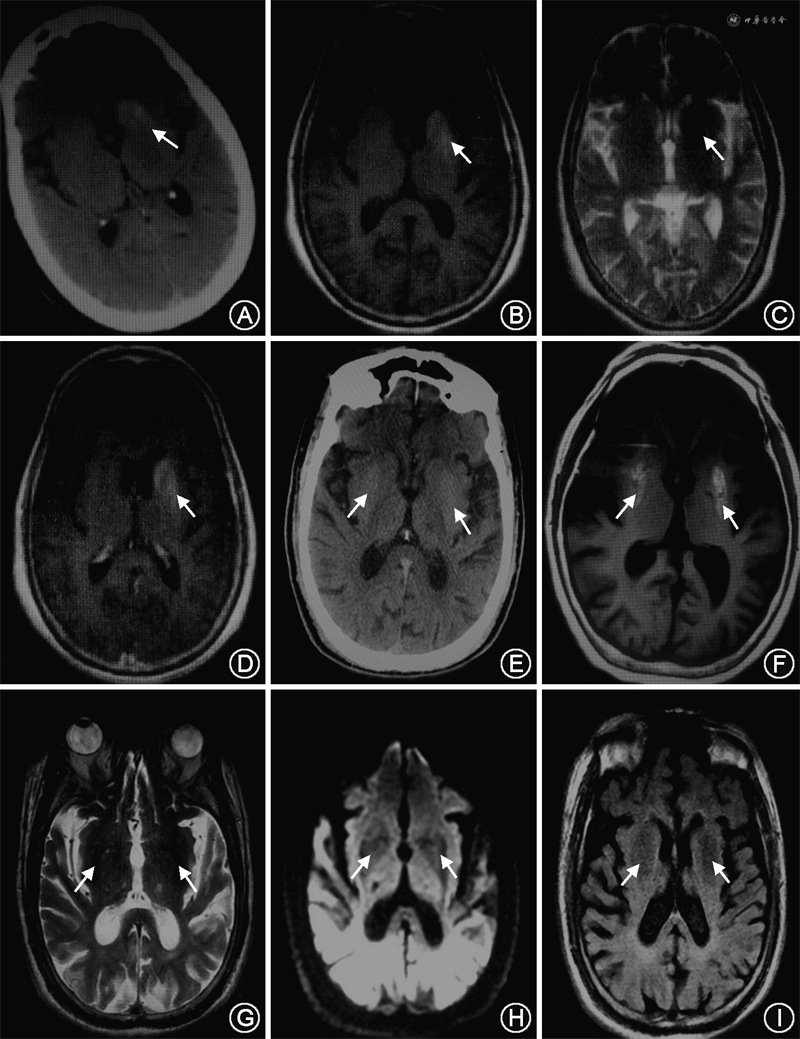

临床资料 例1 患者女性,86岁,因“右侧肢体舞蹈样动作7 d”于2018年9月11日入院。患者7 d前无明显诱因出现右下肢舞蹈样不自主动作,幅度大、无规律,逐渐波及右上肢和右侧面部(下颌),可短时间自控,入眠后消失。既往左上肢骨折术后6年,恢复可。个人及家族史无特殊。入院体检:体温36.4 ℃,脉搏90次/min,呼吸17次/分,血压155/69 mmHg(1 mmHg=0.133 kPa),意识清楚,精神差,言语流利,K-F环(-),右侧肢体及下颌舞蹈样不自主运动,共济体检欠配合,双侧病理征未引出,余神经系统体检未见阳性定位体征。辅助检查:颅脑CT:左侧基底节区片状略高密度影(CT值51 HU)(图1A)。颅脑MRI(图1B~D):左侧基底节区不规则T1WI高信号、T2WI低信号、DWI低信号影,边界清;无强化现象;MRA未见明显血管狭窄。颈动脉血管彩超:双侧颈动脉内-中膜增厚伴斑块形成、双侧锁骨下动脉及椎动脉结构及血流未见明显异常。心电图正常。心脏彩超:三尖瓣轻度反流,射血分数值62%。随机血糖29.4 mmol/L。血酮体(++)。总胆固醇6.10 mmol/L。红细胞沉降率30 mm/h。尿常规:尿糖(+++)、尿蛋白(+)、尿酮体(++)。血气、血常规、凝血、C-反应蛋白、肝肾功能、心肌标志物、尿便常规、病毒五项、甲状腺功能三项、血同型半胱氨酸、电解质、脑钠肽、铜蓝蛋白、血管炎相关免疫全套未见异常。治疗:小剂量胰岛素泵入控制血糖,补液,氟哌啶醇(1 mg、3次/d)对症治疗;第3天血糖正常而改用30/70混合重组人胰岛素注射液,第4天血酮体转阴,第7天舞蹈症状完全控制,患者自动出院。随访:患者出院后因经济条件限制未坚持胰岛素治疗,5 d后右侧肢体舞蹈样动作再次出现,14 d后对侧出现类似舞蹈样症状,最终死于急性肾衰竭。

例2 患者男性,85岁,因“发现行为异常3 d”于2020年10月31日入院。患者3 d前无明显诱因出现双上肢舞蹈样不自主运动、身体不自主扭动,幅度大、无规律,逐渐出现扭头耸肩、双手指伸展抓握、面部挤眉弄眼,紧张时加重,不能自控,入眠后消失。既往有2型糖尿病病史10年,未规律胰岛素治疗,血糖控制差;颈椎椎管狭窄术后3年,恢复可。个人及家族史无特殊。入院体检:体温36.5 ℃,脉搏70次/min,呼吸19次/min,血压165/86 mmHg,意识清楚,精神差,言语流利,K-F环(-),双上肢舞蹈样不自主运动、身体不自主扭动,幅度大、无规律,逐渐出现扭头耸肩、双手指伸展抓握,面部挤眉弄眼,不能自控;共济体检欠配合,双侧病理征未引出,余神经系统体检未见阳性定位体征。辅助检查:颅脑CT:双侧基底节区稍高密度影(CT值49 HU)(图1E)。颅脑MRI(图1F~I):双侧基底节区可见T1WI高信号、T2WI稍低信号、DWI低信号影;无强化现象;MRA未见明显血管狭窄。颈动脉血管彩超:双侧颈动脉内-中膜增厚伴斑块形成、右侧锁骨下动脉起始段内-中膜增厚伴斑块形成、双侧椎动脉结构及血流未见明显异常。心电图正常。心脏彩超:二尖瓣轻度反流,射血分数值60%。空腹血糖22.7 mmol/L,血酮体(++)。尿常规:尿糖(++++)、尿蛋白(-)、尿酮体(+)。血气、血常规、凝血、C-反应蛋白、降钙素原、肝肾功能、心肌标志物、尿便常规、红细胞沉降率、血脂、病毒五项、甲状腺功能三项、血同型半胱氨酸、血氨、电解质、脑钠肽、血管炎相关免疫全套检查未见异常。治疗:小剂量胰岛素泵入控制血糖,氟哌啶醇(1 mg、3次/d)对症治疗,补液,阿司匹林肠溶片(0.1 g、1次/d)抗血小板聚集,舒血宁(20 ml、1次/d)改善循环,阿托伐他汀钙片(20 mg、每晚睡前服用)降脂稳定斑块;血酮体转阴后改为赖脯胰岛素(早5 U、午7 U、晚5 U)、甘精胰岛素(睡前10 U)控制血糖。第5天舞蹈症状完全消失,氟哌啶醇逐渐减量至停药,于第9天出院。随访:出院后15 d内,患者血糖控制在正常范围,未再出现舞蹈样不自主运动。

HC-NH主要累及基底节区,以单侧为主,双侧少见。影像学具有特征性:颅脑CT可见基底节区高密度影(CT值约50 HU),易被误诊为脑出血,给患者带来不必要的经济和心理负担。绝大多数病例磁共振T1WI呈高信号,T2WI信号随检查时间变化表现不一、呈稍低或等信号,DWI呈低信号,增强扫描无强化、不具特征性;不符合通常血肿的时间演变规律,无明显水肿及占位效应,边界清。上述2例患者的发病部位及影像学表现与HC-NH基本相同。

综上所述,酮症性偏侧舞蹈症发病部位及临床表现与HC-NH基本相同,主要累及纹状体,以单侧为主,也可双侧受累;引起病变部位对侧肢体近端、面部及手部不自主运动。影像学特点为颅脑CT基底节区高密度影,磁共振T1WI高信号、T2WI稍低或等信号、DWI低信号、无强化现象。治疗的基础及关键是控制血糖,多数患者的舞蹈症状在数天或数周内随血糖的控制而逐渐好转消失;但如果对血糖控制不积极,可复发甚至累及双侧。对于顽固性病例,可加用多巴胺受体拮抗剂氟哌啶醇,有助于控制舞蹈症状。而该病的具体发病机制尚需进一步研究。我们在临床工作中应对此提高认识,避免误诊误治。